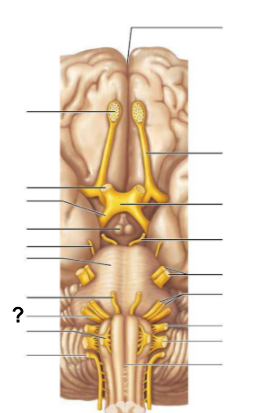

What structure, labeled “?”, is the starting point of cerebrospinal fluid circulation in the brain?

Lateral ventricle

From the lateral ventricles, CSF flows through which structure, labeled “?”, to reach the third ventricle?

Interventricular foramen

After the third ventricle, CSF flows through which narrow passage, labeled “?”, to reach the fourth ventricle?

Cerebral aqueduct

What are the two apertures, labeled “?”, through which CSF exits the fourth ventricle to enter the subarachnoid space?

The median aperture and the lateral apertures

Which structure surrounds the brain and spinal cord, allowing CSF to circulate?

Subarachnoid space

Through which structure, labeled “?”, is CSF absorbed into the venous blood?

Arachnoid villi

Into which venous system does CSF drain after passing through the arachnoid villi?

Dural venous sinuses

What is the function of the central canal in CSF circulation?

It allows CSF to flow through the spinal cord.